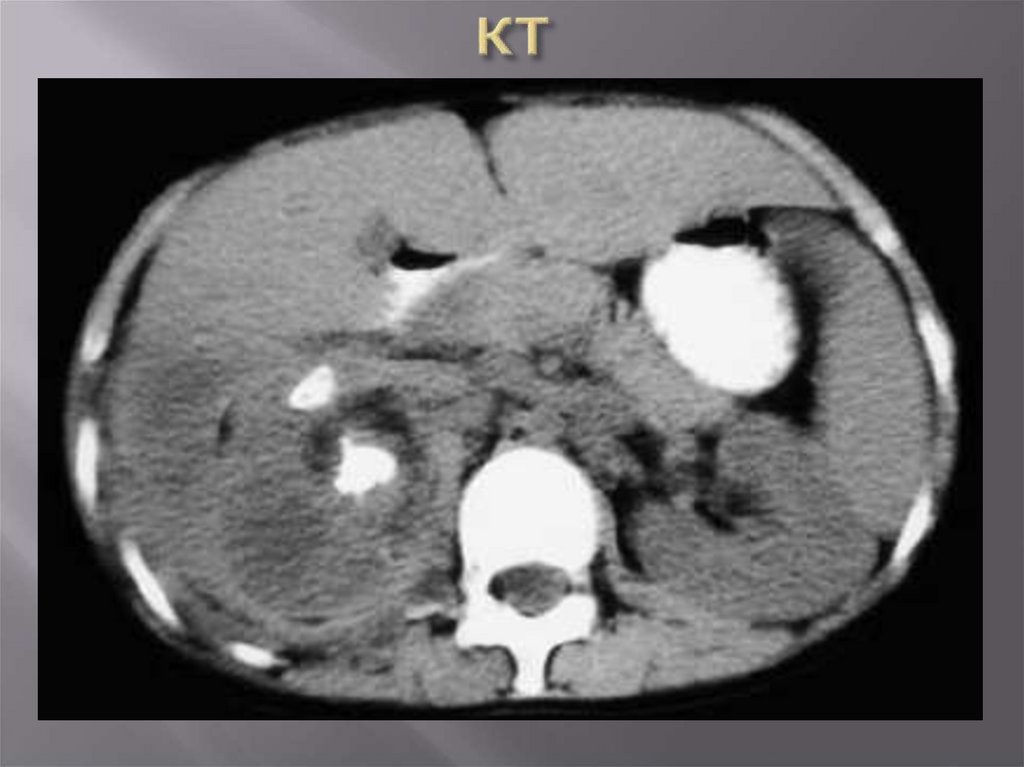

Лучевые методы (УЗИ, допплер,

рентгеноконтрастные методы,

радиоизотопные методы, КТ, МРТ)